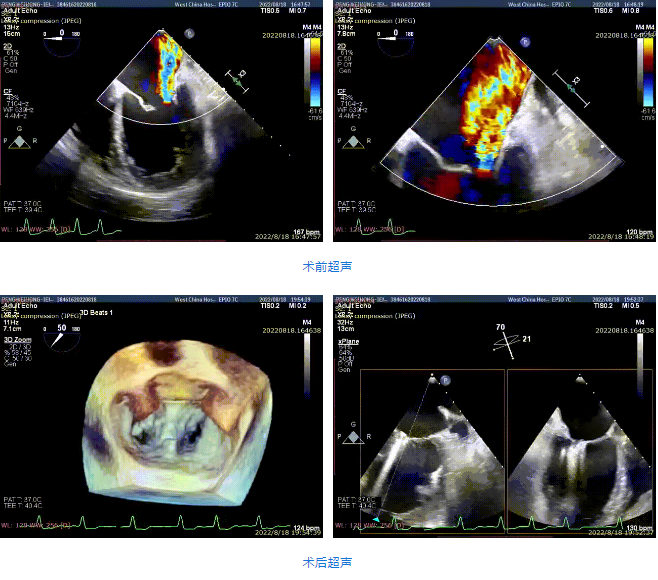

接受治療的是一例59歲男性患者,主訴“心累氣促5余年,加重伴胸痛1個(gè)多月”,已經(jīng)過規(guī)范化藥物治療。術(shù)前超聲提示左心明顯增大,右心稍大。左室心尖部肌小梁增多。室間隔及左室后壁厚度正常,左室后下壁基底段變薄、稍向外膨出,搏幅明顯減弱,余室壁搏幅減低,左室壁整體運(yùn)動(dòng)欠協(xié)調(diào)。二尖瓣瓣尖稍增厚,回聲稍增強(qiáng),后瓣受牽拉,活動(dòng)度差,前瓣關(guān)閉錯(cuò)位,開放尚可。多普勒提示:二尖瓣大量反流(VC=6*18mm,EOA=0.53cm2,Vol=61ml);二尖瓣環(huán)舒張期運(yùn)動(dòng)頻譜呈單峰,EF=30%。

手術(shù)采用全身麻醉插管,經(jīng)股靜脈-房間隔入路,在TEE和DSA引導(dǎo)下完成房間隔穿刺。置入瓣膜夾系統(tǒng)后,在左房調(diào)整瓣膜夾的位置和軸向,后進(jìn)入左室,在TEE引導(dǎo)下捕捉二尖瓣前后瓣葉,并關(guān)閉瓣膜夾。經(jīng)TEE反復(fù)確認(rèn)手術(shù)效果后最終鎖定并釋放瓣膜夾。術(shù)后即刻超聲顯示瓣膜夾位置穩(wěn)定,功能良好,肺靜脈逆流和左房壓都明顯好轉(zhuǎn)。